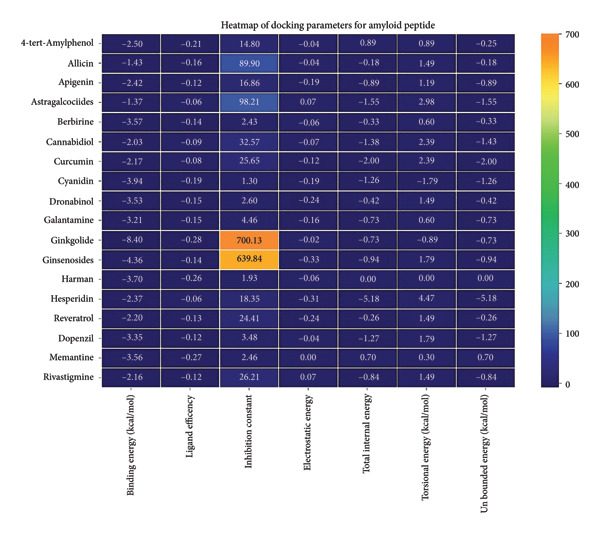

3.4. AutoDock Vina Results: Aβ Peptide

Against the core Aβ peptide, ginkgolide again showed the lowest binding energy (−8.40 kcal/mol), though no direct hydrogen bond interactions were detected in the lowest‐energy pose. Ginsenosides (−4.36 kcal/mol) demonstrated stable interactions, notably forming H‐bonds with ALA4 and LYS2.

Ginsenosides (−4.36 kcal/mol) formed a highly optimal bond with ALA4 (carbonyl oxygen [O] donor) with a short distance (2.56 Ǻ) and a near line angle (160.82°). Cyanidin (−3.94 kcal/mol) also formed H‐bonds with ILE5 and ASN1. The reference drug memantine exhibited significant binding at −3.56 kcal/mol, forming an H‐bond with the critical amyloidogenic residue ILE5 D‐A 2.80 Ǻ, angle: 159.52°. Figure 4 summarizes the binding characteristics for Aβ peptide.

The heatmap in Figure 6 provides a comprehensive visual interpretation of the AutoDock Vina docking analysis of natural ligands (light blue‐coded) and reference drugs (orange‐coded) against four key AD‐related receptors. Ginkgolide consistently demonstrates strong (deep red coloration) binding energies across all four receptors: sortilin (blue‐coded), clusterin (green‐coded), Aβ peptide (yellow‐coded), and tau proteins (purple‐coded). Natural ligands exhibited varied yet significant binding profiles; ginsenosides showed strong affinities for tau proteins and Aβ peptide, with moderate binding to sortilin and clusterin. Dronabinol displayed particularly strong interactions with sortilin and Aβ peptide, while berberine and apigenin consistently showed favorable binding across multiple targets, underscoring their broad spectrum of action. In stark contrast, hesperidin consistently presented among the weakest binding affinities across most receptors (indicated by blue/lighter colors), suggesting limited direct molecular interaction.

Comparative analysis against the established reference drugs—memantine, donepezil, and rivastigmine—revealed that several natural compounds, most notably ginkgolide, achieved binding affinities that were superior to these therapeutic agents across various AD‐related targets, highlighting their significant potential as alternatives or adjuncts. The hierarchical clustering patterns displayed by the dendrograms provided further insights: Molecules grouped together along the y‐axis (ligand–receptor pairs) often shared similar overall binding characteristics. For example, ginkgolide consistently clustered within highly favorable binding groups across multiple receptors (Figure 7), and groups like ginsenosides and cyanidin showed similar strong binding patterns toward tau proteins. Notably, certain natural ligands, such as allicin and harman, clustered with other smaller, more drug‐like natural compounds. Importantly, this clustering also revealed instances where natural ligands exhibited similar binding profiles to reference drugs like memantine, donepezil, or rivastigmine, suggesting potentially shared binding modes or therapeutic mechanisms.